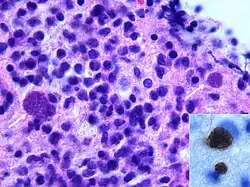

Die Toxoplasmose führt bei Immunsupprimierten (z. B. Neugeborenen, AIDS-Patienten oder Patienten nach allogener Stammzelltransplantation) zu Erkrankungsbildern, die bei Menschen mit intaktem Immunsystem nicht vorkommen. Besonders schwerwiegend ist die zerebrale Toxoplasmose, die sich in Form von großen raumfordernden Prozessen mit entsprechenden neurologischen Ausfällen äußern kann. Manchmal kann die Diagnosestellung schwierig sein, insbesondere die differenzialdiagnostische Abgrenzung zu ZNS-Lymphomen, die bei Immunsupprimierten ebenfalls um ein Vielfaches häufiger auftreten. Die Diagnose kann durch Nachweis der DNS des Erregers im Liquor mittels Polymerase-Kettenreaktion (PCR) oder direkte Hirnbiopsie gesichert werden. Nicht selten muss aber auf Verdacht hin behandelt werden. Medikamente der ersten Wahl sind die Kombination Pyrimethamin+Sulfadiazin (+Folinsäure zur Milderung von Nebenwirkungen des Sulfonamids), oder bei Sulfonamid-Unverträglichkeit die Kombination Clindamycin+Pyrimethamin (+ Folinsäure). Pyrimethamin ist auch in Kombination mit Makroliden wie Azithromycin oder Clarithromycin wirksam.[27] Diese Kombinationen werden aber in den Behandlungsleitlinien nicht empfohlen. Die Therapiedauer beträgt mindestens 4 Wochen. Entscheidender Risikofaktor für das Auftreten einer Toxoplasmose ist die T-Helferzellzahl im Blut. Liegt die Helferzellzahl unter 200/µl, sollte eine medikamentöse Prophylaxe, z. B. mit 960 mg Cotrimoxazol 3 × wöchentlich betrieben werden („Primärprophylaxe“). Ist schon einmal eine Toxoplasmose aufgetreten, muss ebenfalls eine Prophylaxe zur Vermeidung des Wiederauftretens betrieben werden („Sekundärprophylaxe“).[25][26][27]